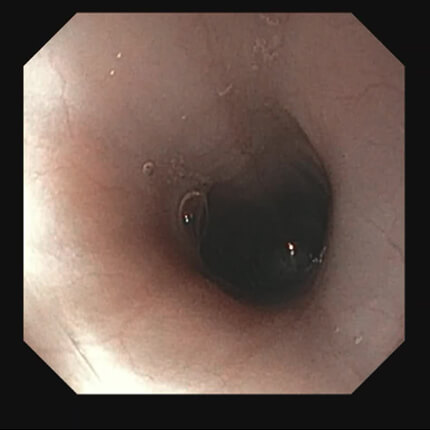

【胃角部】